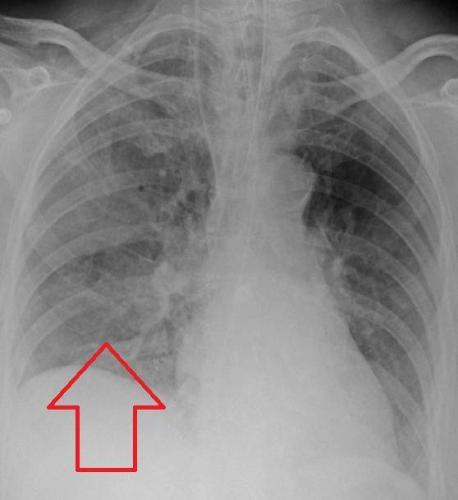

Очаги поражения имеют свойство сливаться, в дальнейшем образуя довольно большую площадь захвата. Строение легкого у малыша подразумевает быструю отечность органа и мобильное формирование патологии.

Помимо ткани легких, воспаление может перейти на плевру, тогда развивается плеврит, который мешает ребенку дышать и доставляет боль.

Иногда, помимо легочной ткани, воспалительный процесс может охватить плевру, что провоцирует развитие плеврита. В особо запущенных случаях на месте воспаления в легких происходит разрушение тканей.

Своевременное лечение при внутриутробной пневмонии позволяет снизить риск развития различных негативных последствий, особенно смерти. Однако даже при всех принятых мерах возможны последствия, которые отображаются в развитии ателектазы или фиброза, что сопровождается спаением участков ткани легких, где формируется соединительная ткань.